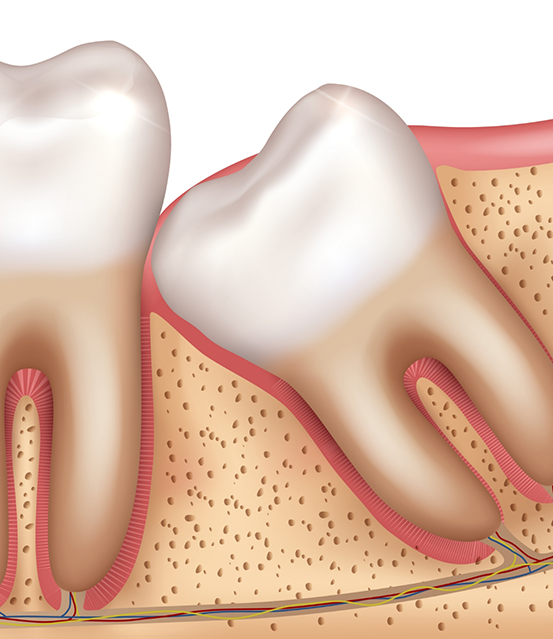

Wisdom teeth, or third molars, can erupt in your late teens and early twenties. Sometimes, these molars do not have enough room to come in properly. It might lead to crowding and infection. Here are some common reasons to get it removed:

- A trapped or partially erupted wisdom tooth can push against your neighboring teeth. You might experience swelling, chronic discomfort, and cysts if left untreated.

- The third molars can damage or shift your second molars. Lack of enough space might lead to root damage and alignment problems.

- Partially erupted teeth are challenging to clean. So they become easy targets for bacterial buildup and gum problems. Removing them can keep your mouth healthy.